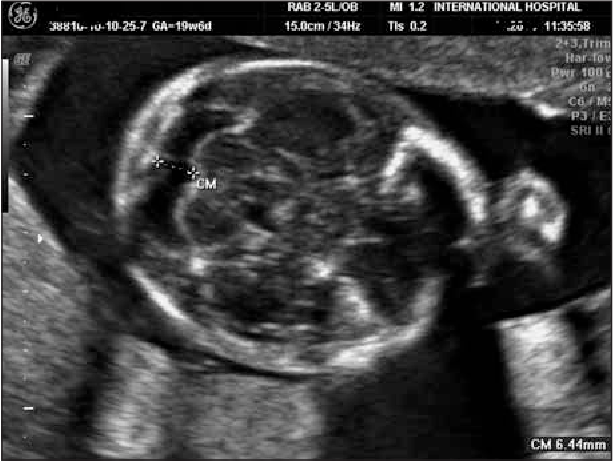

What are we seeing in this image?

Rhombencephalon